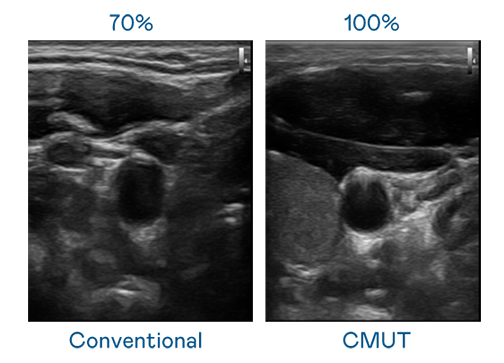

CMUT 技术是一种用电容式微机电元件来产生超音波讯号的技术。与传统 PZT 压电式技术相比,CMUT 频宽增加 30%,更宽频的超音波讯号让影像解析度大幅提升,是实现高影像品质医疗超音波扫描、促进精准医疗发展的关键技术。

超音波影像的解析度高低,首先取决于探头能发出的讯号频宽。伟德国际 CMUT 可提供高清晰的超音波讯号,提供高频宽、高灵敏度、影像纹理细节更高的超音波影像,协助医护人员缩短影像判读时间及利用精准的医疗影像进行诊断。